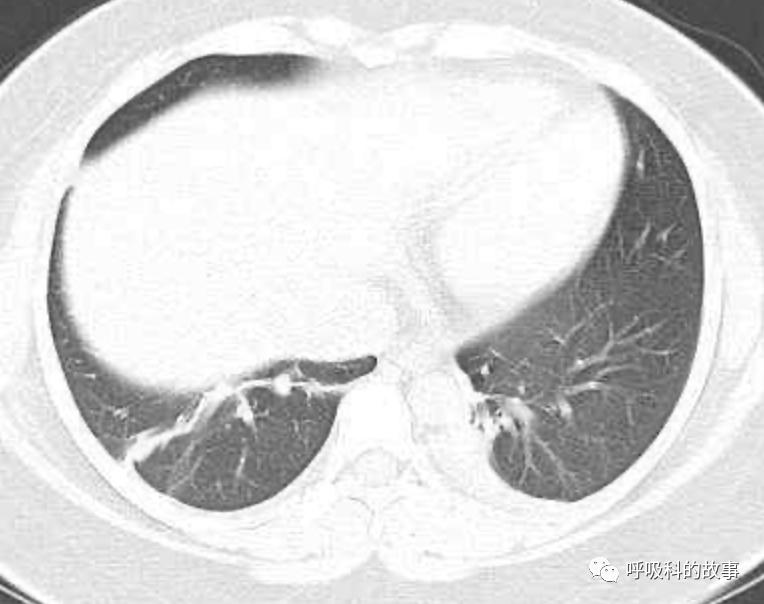

可是在6月26日(往院第18天)仍持续发热的情况下复查肺部CT,肺部病灶已明显吸收了。那么患者发热的原因到底是什么呢?为什么患者高热的情况下血白细胞不升反降,C反应蛋白也没有明显增高?这个时候消化科医生也迷茫了,这可怎么办?于是请感染科和呼吸科医生一起会诊,共商计策。